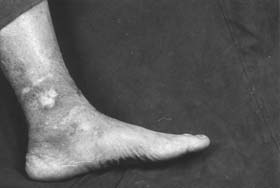

图2

方老先生有多年糖尿病史,一次穿新皮鞋擦伤左脚内踝皮肤(见图2),先是自己敷药,后经多家医院诊治,结果溃口越治越大似杯口状。王先生每次细心地为他擦洗去脓液,剔除腐肉,敷上自制的药膏,并配合活血散瘀、清热消炎的中药内服。经过半年的治疗,终于完全恢复。